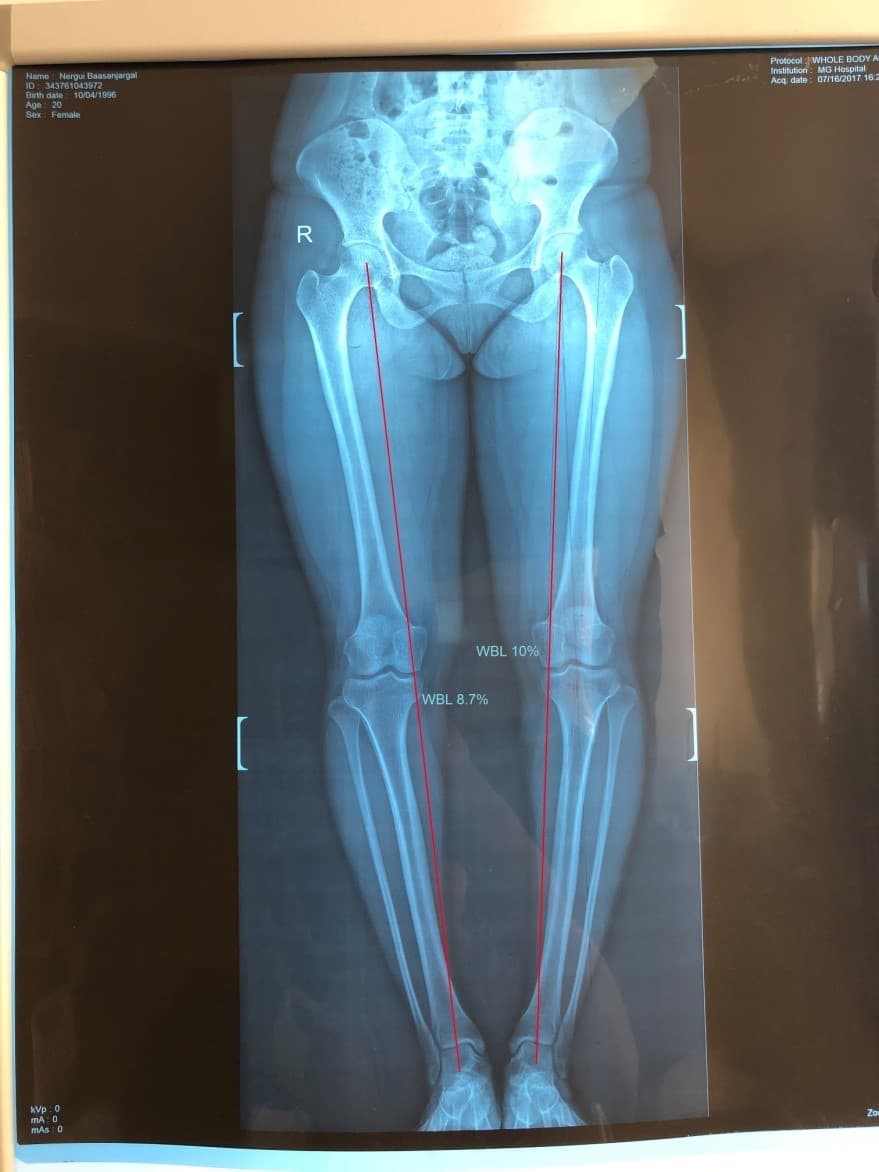

Түнхний төрөлхийн дутуу хөгжил, мултралын улмаас хоёр түнхний үеийг солих мэс засал хийгдсэн эмчлүүлэгчид хийгдсэн саруй хөл засах мэс заслын өмнөх болон дараах рентген зураг

Саруй хөл нь ихэвчлэн өвдөгний гадна хэсэгт ирэх ачааллыг нэмэгдүүлж өвдөлт зовиур үүсгэдэг тул засагдсанаар өвдөгний остеоартритын явц удааширч, өвдөлт зовиур арилж, хөл тэгширч, хөлийн урт богины зөрүү багасдаг.